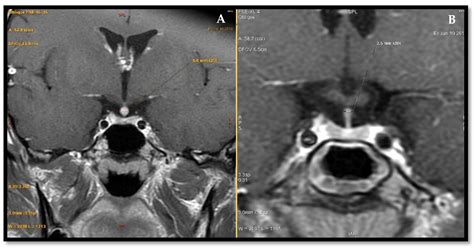

When investigating the pituitary with infundibular stalk, clinicians often look at the thickness and signal intensity of the stalk on imaging tests like MRIs. A thickened stalk can be an early indicator of inflammatory processes, infiltrative diseases, or tumors, emphasizing why this tiny anatomical feature is so vital for diagnostics.

Medical imaging has transformed our ability to examine the pituitary with infundibular stalk in a non-invasive manner. Modern high-resolution MRI scans are the gold standard for identifying potential pathology in this region. Radiologists specifically look for symmetry, the position of the optic chiasm, and the integrity of the stalk itself.

• Infundibuloneurohypophysitis: A rare inflammatory condition specifically affecting the stalk and the posterior pituitary.

• Ectopic Pituitary Gland: A condition where the pituitary gland develops in an abnormal location, often due to an absent or truncated infundibular stalk.